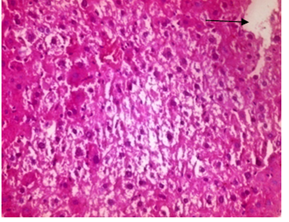

Fig. 3B and 3C represent Mal+ PPE and Mal +PJ groups, respectively. In which the PPE and PJ showed slight effect to overcome the Mal damage to liver tissues. In which, Mal +PPE group showed swollen hepatocytes with foamy finely granular cytoplasm (arrow), while Mal +PJ group showed dilated mildly congested central veins (arrow head), ground glass hepatocytes (arrow) and inflammatory cells appeared in different parts of the hepatic tissue. The effect of PPE and PJ co-administration with Atra, on liver tissue is represented by fig. 3D and 3E, respectively.

They show a mild ameliorating effect of PPE or PJ on liver tissue, that was represented by tissue cords of hepatocytes with mild fatty change in the form of central nuclei surrounded by vacuolated cytoplasm(arrow) for Atra+PPE group and also a moderate fatty changes in the hepatocytes for Atra+PJ group (arrow). Moreover, PPE and PJ combined co-administration with Mal + Atra shows tissue cords of hepatocytes with mild congestion surrounded by vacuolated cytoplasm (arrow) as showed in fig. 3F.

Fig. 3: Photomicrographs of liver section of different mice groups. In which A, represents PJ group; B, Mal + PPE group; C, Mal + PJ group; D, Atra + PPE group; E, Atra + PJ group and F, Mal +Atra + PPE + PJ group. H&E (X200)